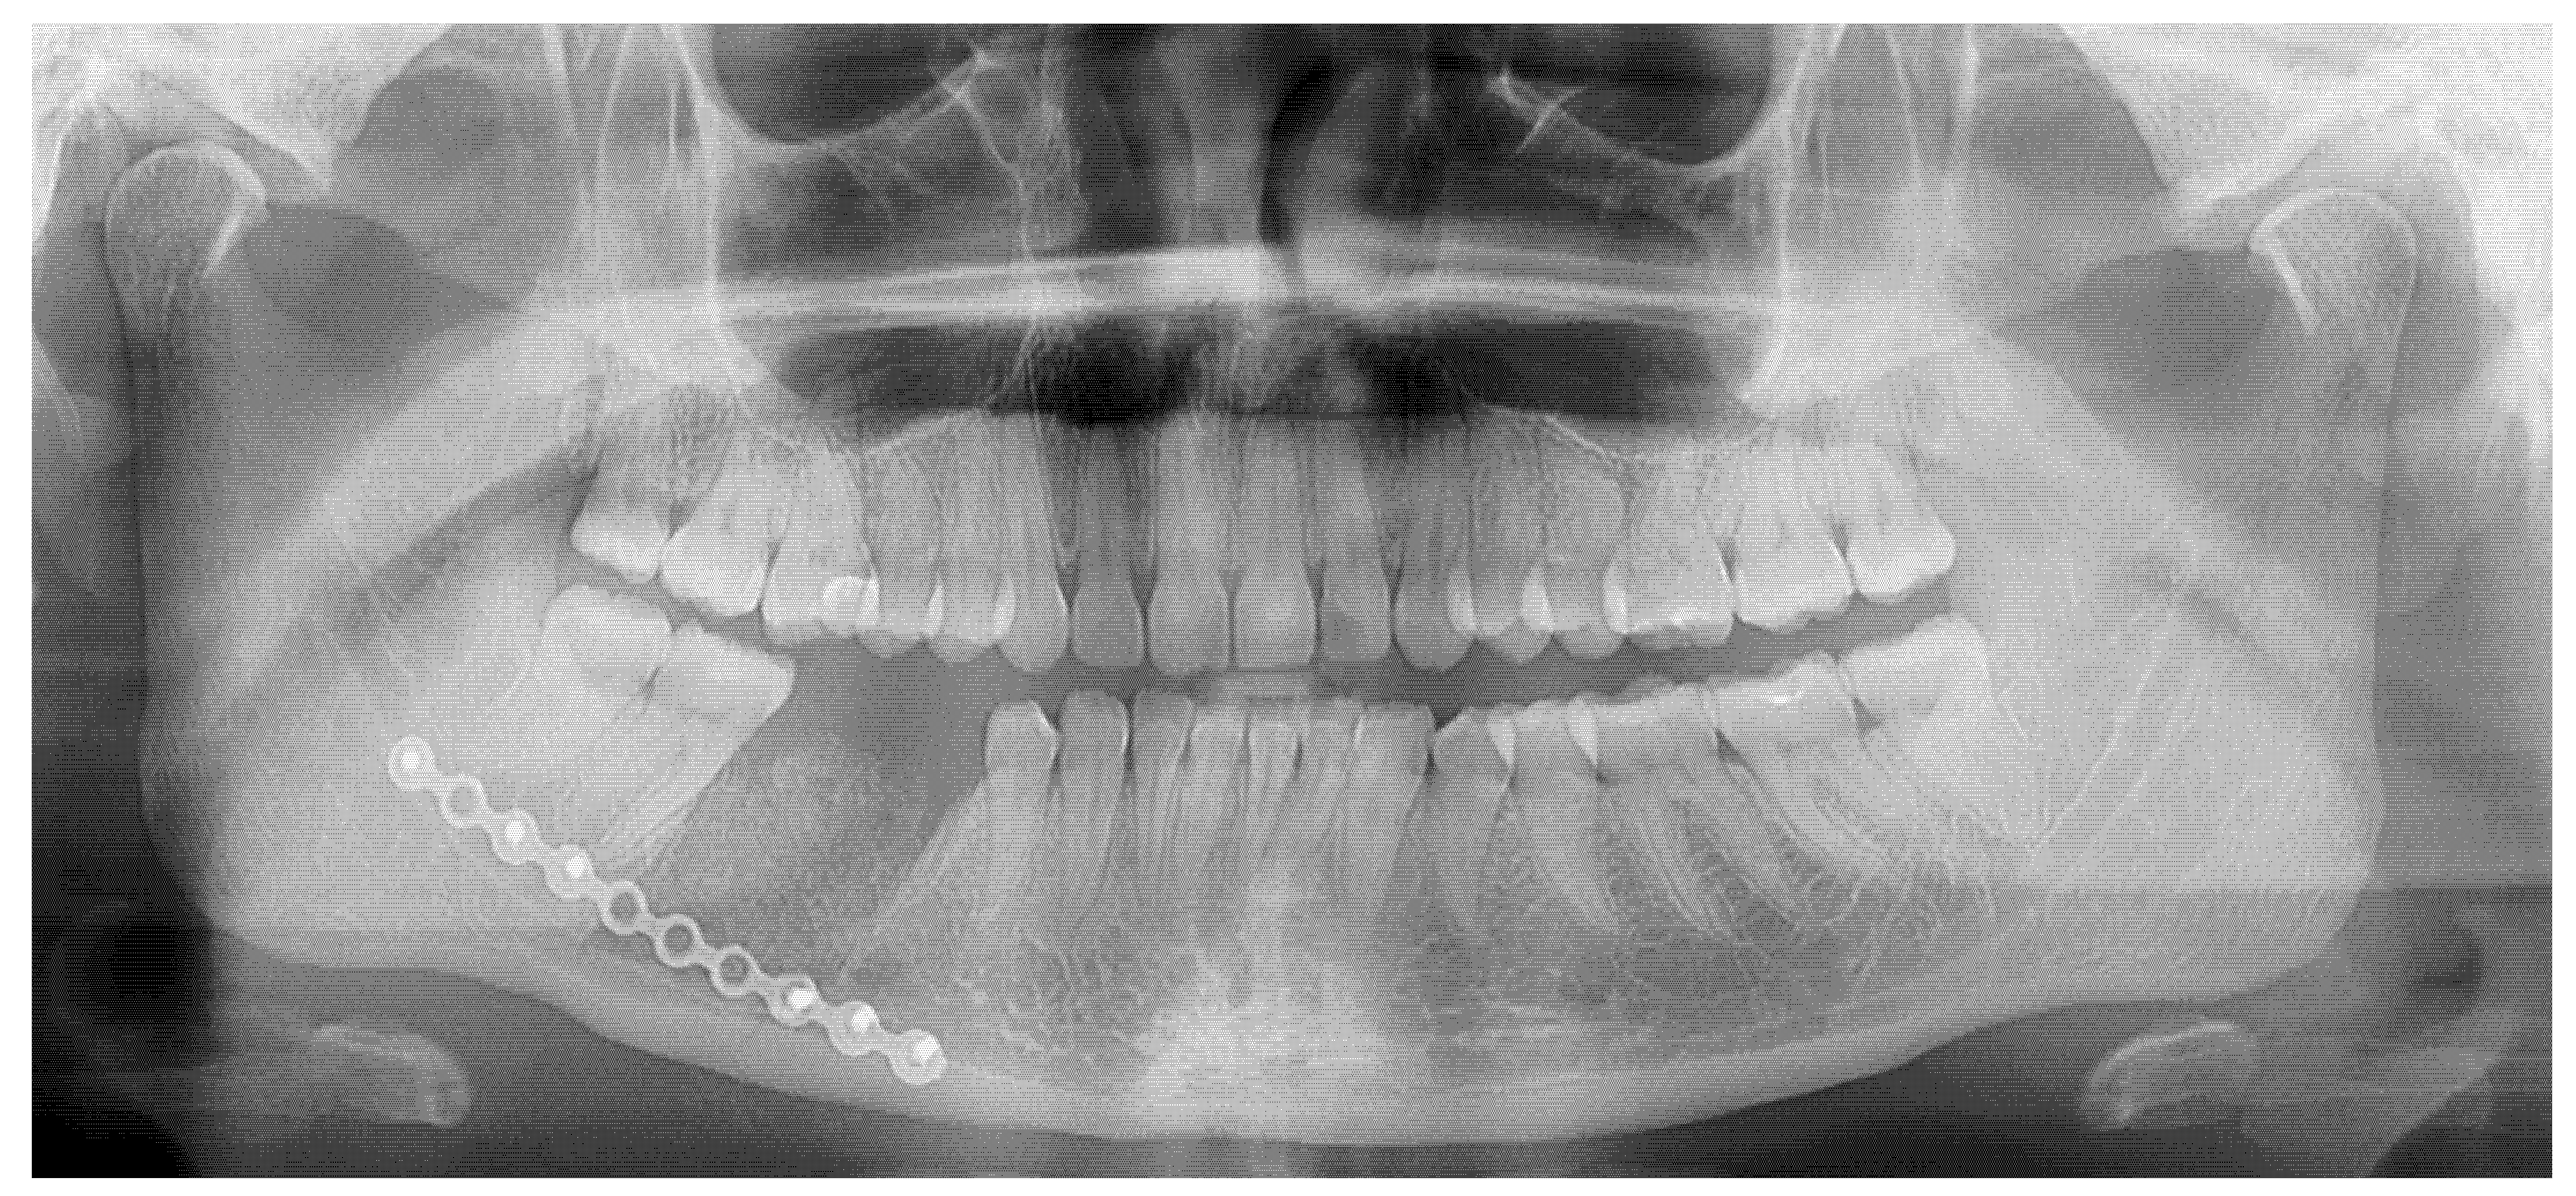

Figure 1. The occurrence of different irregular radiolucent areas on panoramic radiographs (panx) is quite a typical finding. Most are related to periapical teeth lesions, granulomas, odontogenic cysts, or other conditions. The occurrence of osseous, fibrous, or fibro-osseous lesions (cemento-osseous dysplasia, ossifying fibromas (their types psammomatoid, juvenile), and fibrous dysplasia (DF) in the mandible requires improved diagnostics with CBCT—cone beam computed tomography. A classic panoramic radiograph has many limitations in fully investigating each bone lesion in the jaw. Assessing the status of dental roots (displaced, resorption), the cortical buccal and lingual plates (expansion, swelling, erosion), the presence of periosteal reaction or elevation, and the shape, size, and status of adjacent teeth might be quite limited. The occurrence of ossifying fibroma (OSF) might be misdiagnosed as certain bone dysplasias, odontogenic cysts, or cemento-osseous dysplasia (COD) at various stages of maturation and calcification. It may also be mistaken for static bone cavities (SBCs) or even overlooked on panx. In some cases, similar bone cavities might be associated with other bone pathologies like brown tumors in hyperparathyroidism or other thyroid, parathyroid, and pituitary gland anomalies related to calcium–phosphorus metabolism [1,2,3]. The first step should always include improved diagnostics, followed by a scheduled biopsy—such as incisional biopsy—or lesion observation. Improved diagnostics may include SPECT (single-photon emission computed tomography) or, to exclude any metabolic disorders, a complete blood panel that examines calcium–phosphorus metabolites (serum calcium concentration (Ca), parathyroid hormone (PTH), active vitamin D (1,25(OH)2D), magnesium, blood phosphorus levels, bone alkaline phosphatase, thyroid hormones such as thyroxine (T4) and triiodothyronine (T3), and TSH [1,2,3]). The presented panx shows a radiolucent, irregular area under tooth 46 (the lower right first molar) without a clear border (red arrow), adjacent to the superior part of the mandibular canal, without any clear teeth resorptions or displacements.